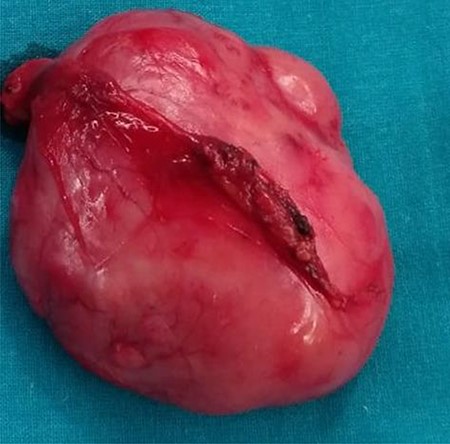

During the surgery, the mass was identified at pre-vesical region (extra peritoneum) firmly attached to the pubis, in vicinity with the bladder, displacing it but without infiltration, so bladder resection was not needed (Fig. 3).

Macroscopic description: round and smooth brownish well delimited 6 cm in diameter solid lesion with homogeneous fibrous appearance. No signs of macroscopic necrosis are evident.